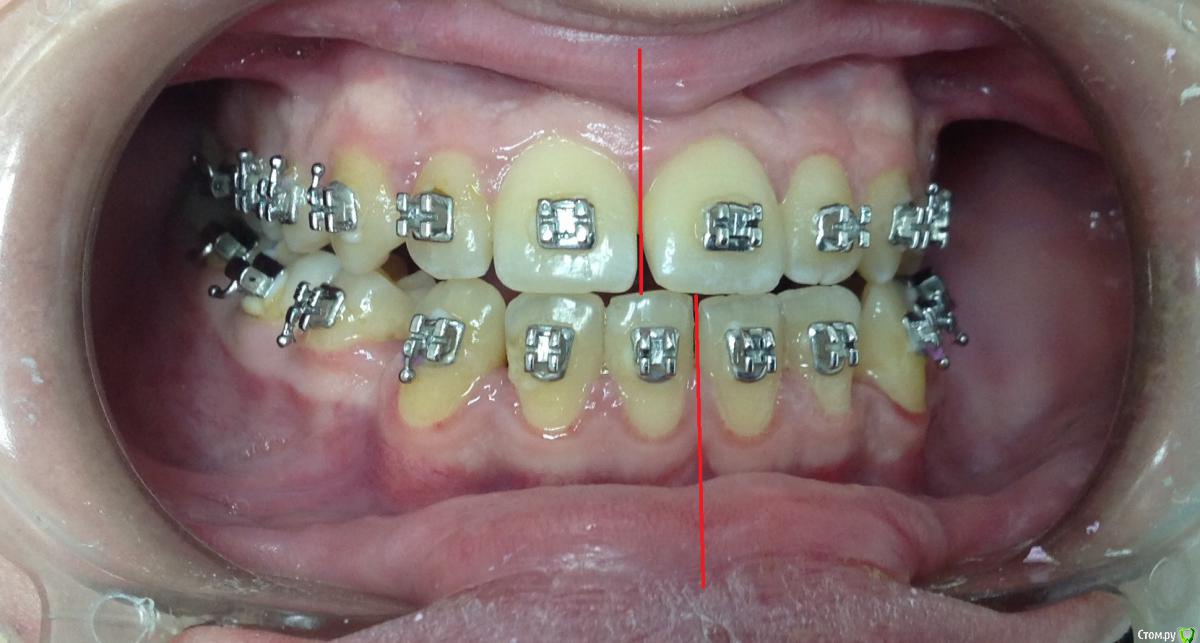

KoroNa Опубликовано 13 января, 2015 Поделиться Опубликовано 13 января, 2015 Здравствуйте. Опыт у меня совсем небольшой, можно даже сказать никакой на данном этапе. Пациент достался "по наследству" от подруги. Приехал учиться в наш город, она и пристроила мне. Я делала свое дело, меняла лигатурки, зная, что пациент периодически ездит в свой город и будет контроль лечения со стороны моей коллеги. А та, не долго думая, в декрет укатила с двойней. Когда увидела пациента, то как РАДА НЕ БЫЛА - ничего не сказать.3класс. вертикальный тип роста. Явные признаки к комплексному орто\хир лечению. Но она взялась, пожалела\попросили.....удалила премоляры на н\ч и начала дистализацию. Никаких ТРГ и моднлей в помине нет, да и я еще когда брала его даже фотографии не делала.Не хочу на форуме ругаться, но пациент "какашка" .......гигиенты нет как в полости рта, так и на лице...пропуски приемов....и т.д.НО! Подруге пообещала....Я сразу написала, что опыта ноль, только благодаря нашим лекторам стала сейчас обращать внимание на симметрию, на сустав и т.д. И вот, заходит пациент, на очередную смену лигатур, такой красивый в кабинет и что я вижу.....нижняя челюсть смещена влево, явная асимметрия. Куда мои глаза и мозги смотрели. Очень прошу помочь мне советами, что сейчас нужно сделать, с чего начать Ссылка на комментарий

KoroNa Опубликовано 14 января, 2015 Автор Поделиться Опубликовано 14 января, 2015 Начните с диагностики. Rg-снимки есть? считали ТРГ? фото в профиль не помешает и смыкание зубов с противоположной стороны. Когда пациент открывает максимально рот, средние линии совпадают, или есть хотя бы стремление к этому? соберите данные все.И вообще- пациента это смещение сильно беспокоит?)) Спасибо за ваш быстрый ответ.Фото в профиль есть, а вот смыкание зубов слева не получился снимок. Постараюсь переделать. Снимков нет, отправила на ТРГ. При открывании рта среднии линии начинают более-менее совпадать. Пациента не беспокоило это пока я не с акцентировала на проблеме. Он стал жевать на левой стороне и впервые за все время у него появились щелчки в суставе. Ссылка на комментарий

KoroNa Опубликовано 20 января, 2015 Автор Поделиться Опубликовано 20 января, 2015 Думаю паниковать пока рано. Такое иногда бывает при значительном перемещении зуба/зубов, когда возникают контакты бугор-в-бугор, а н.ч отвечает компенсаторным смещением в ту или иную стогону. Если ЦЛ н.ч при максимальном оркрывании рта мигрирует, то всеОК. В любом случае проведите полную диагностику, а ОПТГ сейчас сделайте в положении ЦО (при полном/максимальном смыкании зубов). Это даст возможность оценить симметрию СГ.PS с какой целью стоит лингвальная кнопка на в.ч, носит ли пациент эластики и если да то как?Здравствуйте.Центральная линия при максимальном открывании рта практически "централизуется", но там есть еще и смещение ЦЛ из-за миграции резцов влево."ОПТГ сейчас сделайте в положении ЦО (при полном/максимальном смыкании зубов" - т.е. объяснить пациенту чтобы сомкнул рот на все зубы как смыкает обычно? не нужно смещать челюсть и делать прикусной шаблон?Кнопка справа на 6ом моляре применялась для устранения перекрестной окклюзии. пациент оторвал замок и около месяца не появлялся на прием. вот зуб и уехал. Ссылка на комментарий

Maverick Опубликовано 1 марта, 2015 Поделиться Опубликовано 1 марта, 2015 (изменено) Переместить зубы в положение которое было запланировано изначально, справа поработать с перемещением, потом слева дотянуть, чтобы получить хорошие контакты, плюс полноразмерную стальные дугу можно расширить немного если есть необходимость в этом. Фото фронтальное сделано неправильно и дает неверную информацию, искажая данные. Хорошо было бы взглянуть что было до начала лечения. Хороших окклюзионных контактов все равно не получится в итоге. Изменено 1 марта, 2015 пользователем Maverick Ссылка на комментарий